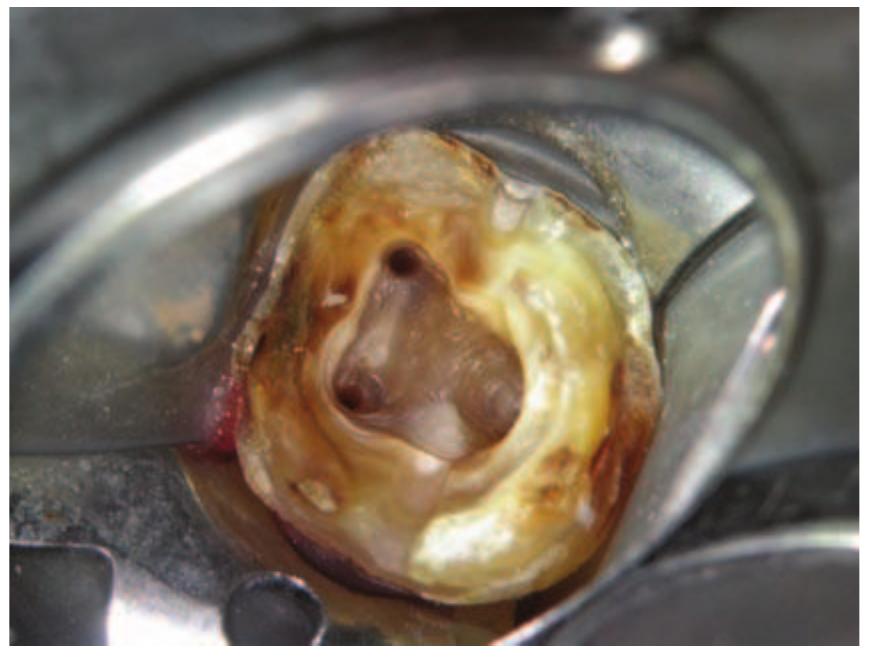

- An attempt at root canal treatment has been made but the root canals are extremely fine and have not been successfully negotiated.

- This can then be placed into the root canal.